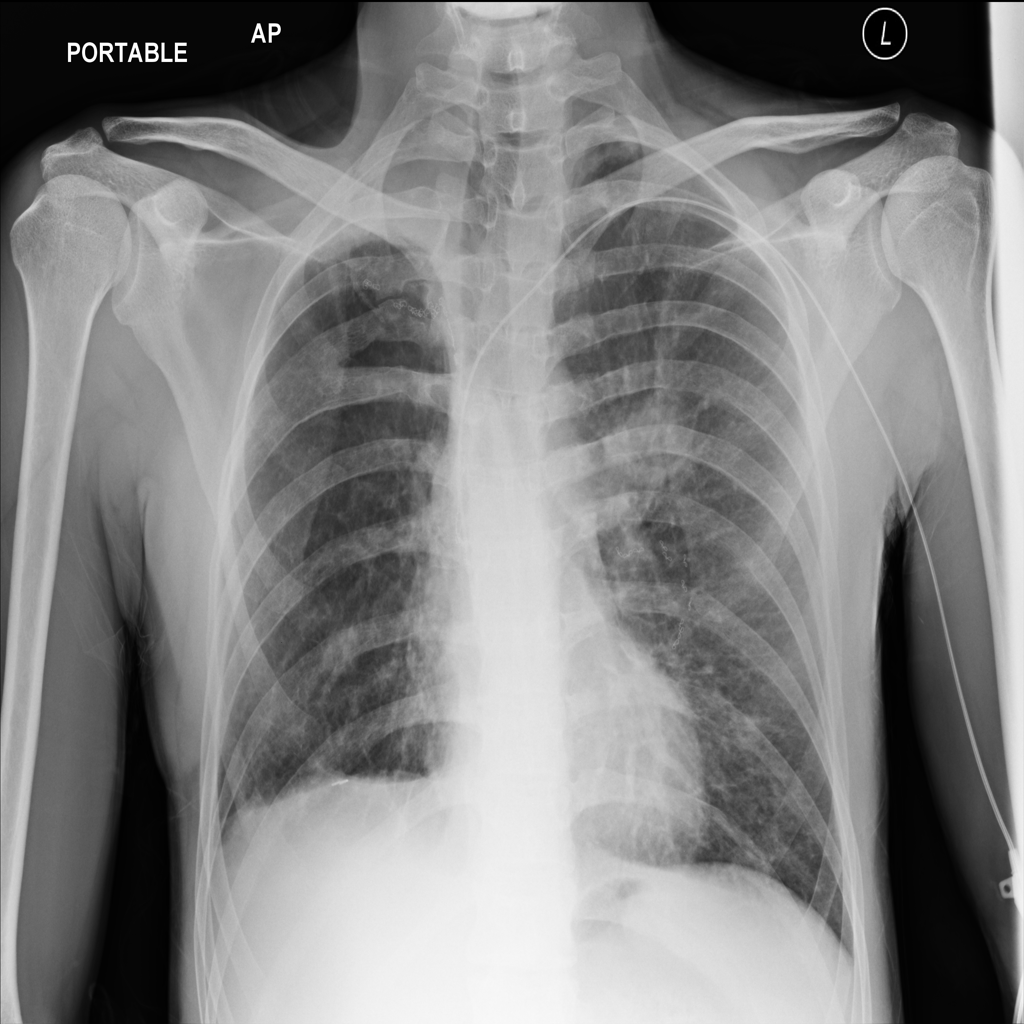

Mass

A mass is a larger focal opacity or lesion seen on the image. It is a descriptive finding that can have several causes and usually needs more imaging or clinical context to characterize.

PAT-1446 · IMG-003Mass

PAT-1446 · IMG-003

AP